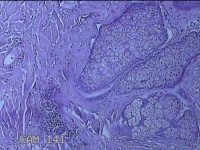

头皮结节

性别

男

年龄

33岁

临床诊断

皮肤赘生物

一般病史

发现头皮结节半个月余,无明显疼痛及不适。

标本名称

大体所见

灰白暗红色带皮肤样结节1x0.8x0.3cm一个,表面糜烂,切开结节呈实性,切面灰白粉红色,质软。

图2